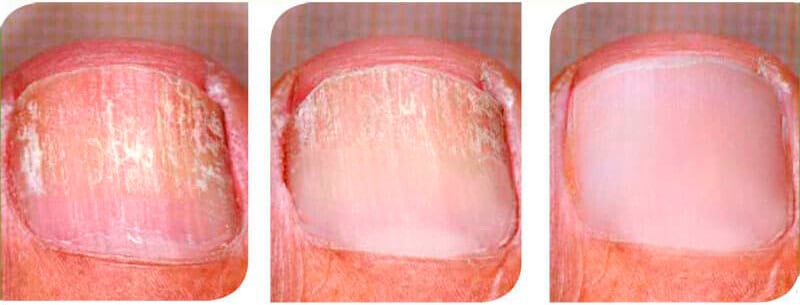

Inicio del tratamientoDos semanas después de comenzar el tratamiento.Cuatro semanas después de iniciar el tratamiento